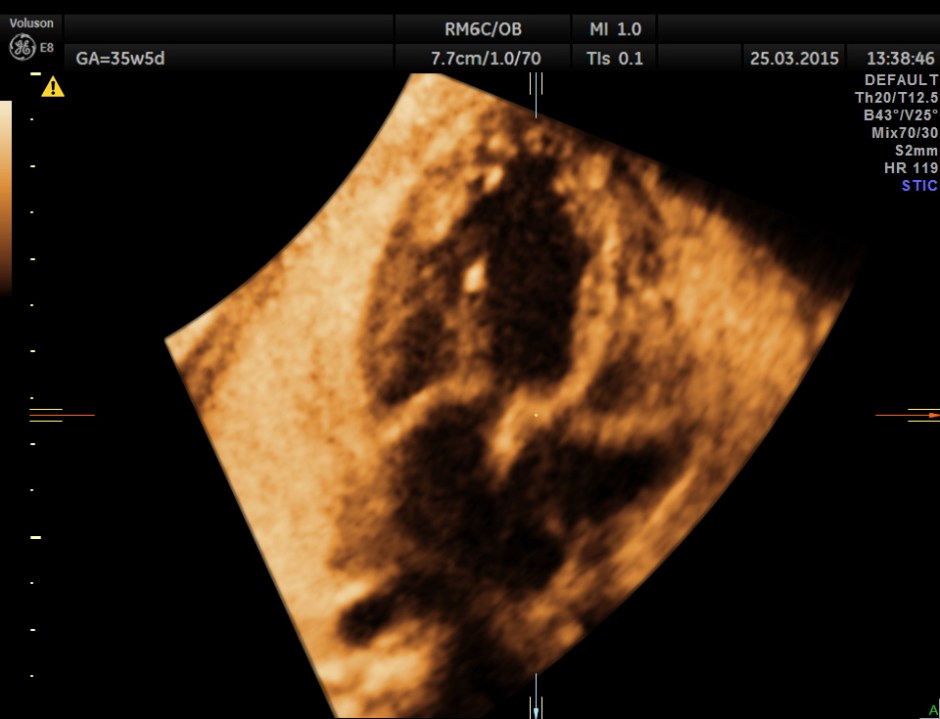

This is a 3 D image showing similar findings. Both pictures also show the pulmonary veins draining into left atrium and the left atrium opening into left ventricle and the right atrium opening into right ventricle. ( free wall attachment of the mitral valve leaflet,moderator band seen in the right ventricle and the tricuspid shows a septal leaflet.)

This shows normal veno atrial and atrial ventricular connections ( concordance ) and ventricular arterial switched connections (discordance).